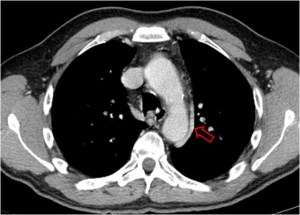

SIGNO DEL ANILLO

Signo de tromboembolismo pulmonar (TEP) en el angioTC con contraste intravenoso. El anillo (flecha) corresponde al contraste que rodea a un trombo central en un vaso cortado transversalmente. Vemos este signo en la arteria lobar inferior derecha. El signo del anillo se ve en el TEP agudo, ya que el trombo ocupa una posición central en el vaso. En el TEP crónico el trombo se hace marginal.